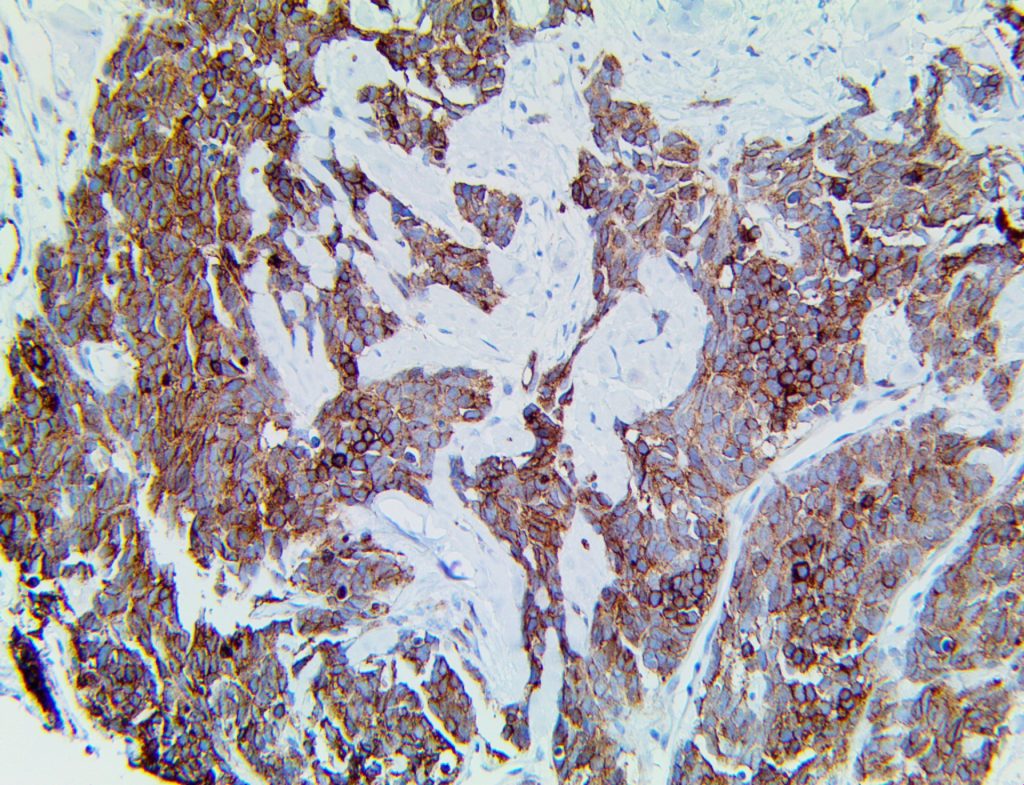

The first cytokines released are interleukin 1β (IL-1β) and tumor necrosis factor-α (TNF-α), which attract a variety of circulating white blood cells (WBCs) to the infection site, including neutrophils, monocytes, macrophages, and natural killer (NK) cells. This response, along with the antipathogenic chemicals released by these cells (i.e., complement), comprise the innate immune response. These cells directly attack the invading pathogen and also release additional cytokines, chief among them interleukin-1 and 6 (IL-6). IL-6 is essential for invoking the adaptive immune response, which calls T-cells, B-cells, and T helper (Th) cells to the infection site. IL-6 also stimulates further recruitment, proliferation and activation of macrophages.

It is the ICU physician who is most likely to witness one of the deadliest manifestations of the abnormal immunological response, the cytokine storm syndrome (CSS). This response is also referred to by some as the cytokine release syndrome (CRS). CSS is characterized by continuous activation and expansion of macrophage and lymphocyte populations, which secrete large amounts of cytokines, causing the cytokine storm. This massive cytokine release is akin to hemophagocytic lymphohistiocytosis (HLH) disease, a syndrome characterized by initial unchecked and persistent activation of cytotoxic T lymphocytes and NK cells.